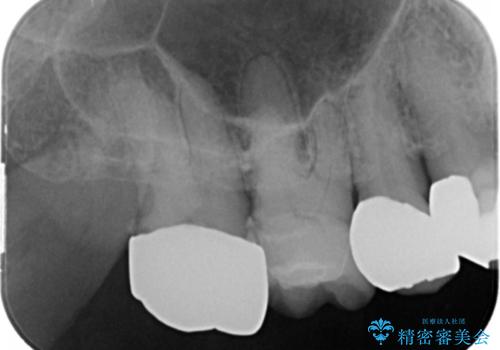

精査したところ、右上奥の銀歯(右上7)は適合不良により二次う蝕になっていました。

銀歯を外してう蝕を丁寧に除去したのち、オールセラミッククラウンによる補綴治療を行いました。